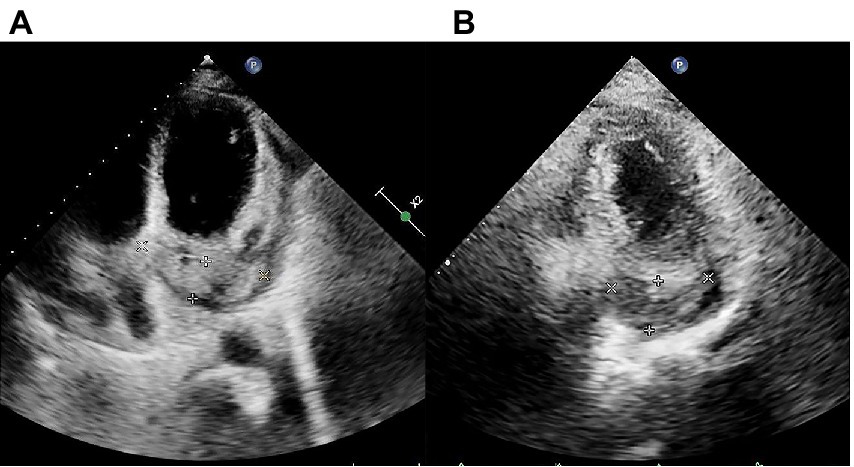

The initial electrocardiogram (ECG) revealed a third-degree AVB, complete right bundle branch block, and junctional escape (Figure 1A). Transthoracic echocardiography (TTE) showed cardiac occupancy, left ventricular diastolic dysfunction, and pericardial effusion (Figure 2A). The patient was later admitted to the Department of Cardiology of our hospital with third-degree AVB and cardiac occupancy. 18F-fluorodeoxyglucose (FDG) positron emission tomography computed tomography (PET-CT) indicated the presence of multiple soft tissue nodules/masses in the pericardial cavity and high FDG uptake in the mediastinal lymph nodes, both suggesting a high probability of malignant lesions and possibly lymphoma (Figure 3). The patient was considered at high risk of tumors, so specialists from chemotherapy, hematology, and respiratory departments were consulted regarding the development of a biopsy protocol for the case. The patient was then transferred to the chemotherapy unit.

Figure 2

Transthoracic echocardiography (TTE) findings pre- and post-chemotherapy. (A) Pre-chemotherapy TTE revealing filling of the coronary sinus with inhomogeneous echogenic material measuring approximately 21.4 mm × 68.3 mm. (B) TTE after the second cycle of chemotherapy showing filling of the coronary sinus with inhomogeneous echogenic material measuring approximately 22.5 mm × 43.4 mm are shown.

Considering the presence of third-degree AVB and the potential cardiotoxicity of anthracyclines, R-COP (rituximab, 600 mg on day 0; cyclophosphamide 1.3 g on day 1; vincristine, 5 mg on day 1; prednisone, 100 mg on days 1–5) was administered for the first cycle of chemotherapy. Two days later, the patient developed heart failure afterwards and his AVB still existed. Therefore, considering the opinion of the cardiology department and the patient’s own request, the patient subsequently underwent leadless pacemaker implantation (Micra) (Medtronic, Inc. Minneapolis, Minnesota, United States). As the patient’s cardiac symptoms faded and AVB disappeared (Figure 1B), a standard R-CDOP regimen was initiated (rituximab, 600 mg on day 0; cyclophosphamide, 1 g on day 1; doxorubicin liposomes, 20 mg on day 1; doxorubicin liposomes, 40 mg on day 2; vincristine, 4 mg on day 1; prednisone, 60 mg on days 1–5). Chest tightness and wheezing weakness were relieved after treatment, and echocardiography showed that the neoplasm on the pericardium also decreased in size (Figure 2B).